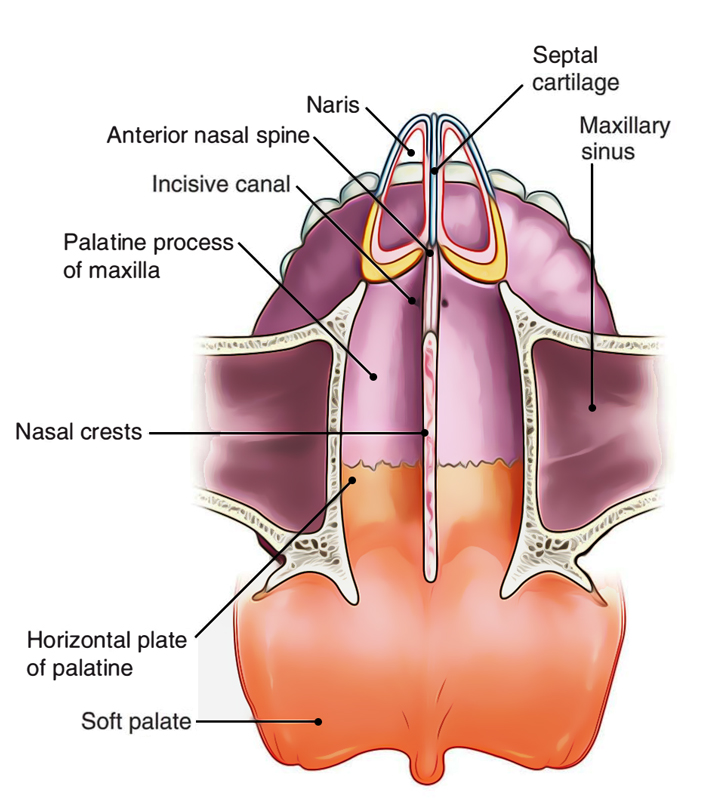

Anatomical Structure Of The Nasal Cavity Through A Vertical

Anatomical Structure Of The Nasal Cavity Through A Vertical

Supportive Bones And Cartilages Of The Nasal Cavity

Supportive Bones And Cartilages Of The Nasal Cavity